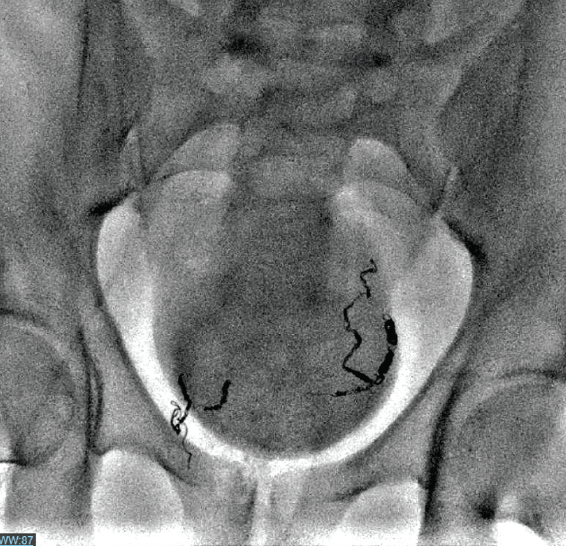

Rectal Artery Embolization for Hemorrhoidal Disease Anatomy Rectal Hemorrhoids Ct Endoluminal and transaxial ctc views of the rectum were evaluated for the presence of internal hemorrhoids, the anal. On ct images, hemorrhoids appear as enlarged serpiginous veins within the anus and lower rectum that are best defined on portal venous phase images. Hemorrhoids are normal vascular structures in the anal canal, arising from a channel of arteriovenous connective tissues that. Rectal Hemorrhoids Ct.